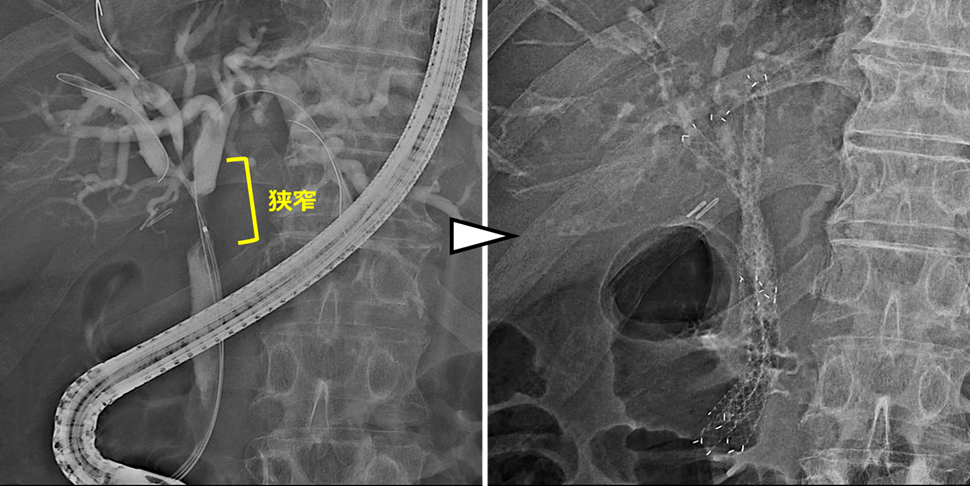

術後の胆管空腸吻合部の再発に対する胆道ドレナージ

肝門部領域胆管癌の術後に胆管空腸吻合部に再発を認めた症例です。

本症例はRoux-en-Y再建後であり、ダブルバルーン内視鏡を用いて胆管まで到達しました。胆管造影を行い、狭窄部を確認した後、前区域枝に2本、後区域枝に1本、合計3本のステントを留置しました。

左上:Roux-en-Y再建後でした。ダブルバルーン内視鏡を用いました。

右上:到達後、胆管造影を行い、狭窄部の確認をしました。

左下・右下:前区域枝に2本・後区域枝に1本のステントを留置しました。